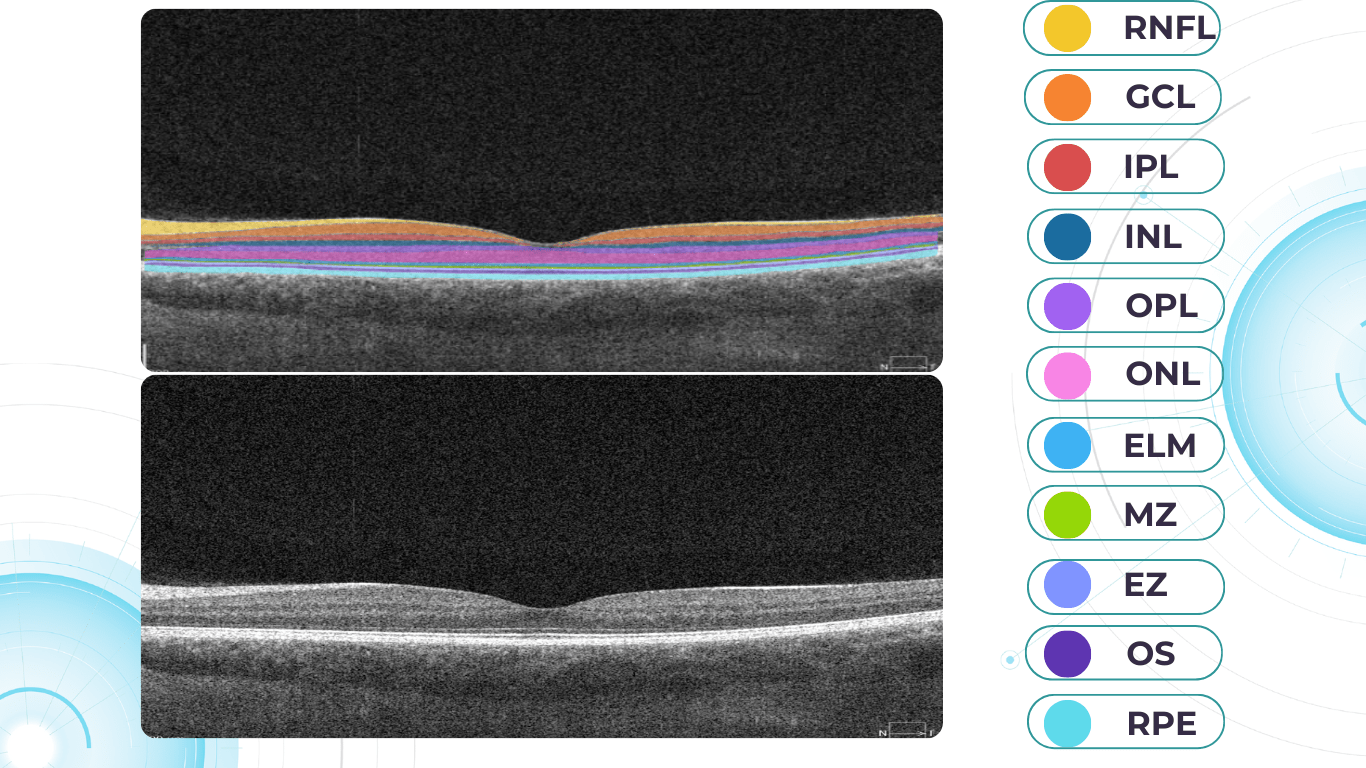

What does diabetic retinopathy look like on OCT?

On OCT, diabetic retinopathy (DR) can appear as a combination of retinal structural damage, fluid accumulation, and microvascular changes that may not be visible on fundus photography.

Typical OCT findings in DR include:

• Photoreceptor damage – loss of outer retinal layers, especially the ellipsoid zone

• Intraretinal hyperreflective foci, hard exudates

• Microaneurysms – visible as small, round changes within the retina

• Retinal thickness changes and neuroepithelial layer atrophy

• Diabetic macular edema  – with intraretinal hyporeflective cystoid spaces and neuroepithelial swelling

• Subretinal fluid  – resulting from increased vascular permeability

• DRIL – disorganization of inner retinal layers, associated with poor prognosis

• Epiretinal membranes – potential precursors to retinal detachment

Diabetic retinopathy screening OCT

Diabetic retinopathy (hyperreflective foci, moderate destruction of the ellipsoid zone and RPE), diabetic macular edema (neuroepithelium edema, intraretinal cystic cavities), epiretinal membrane